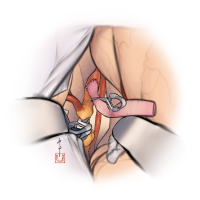

監修:谷川 緑野 / 札幌禎心会病院脳卒中センター

術後イラストシリーズ

監修:太田 仲郎

監修:永田 雄一